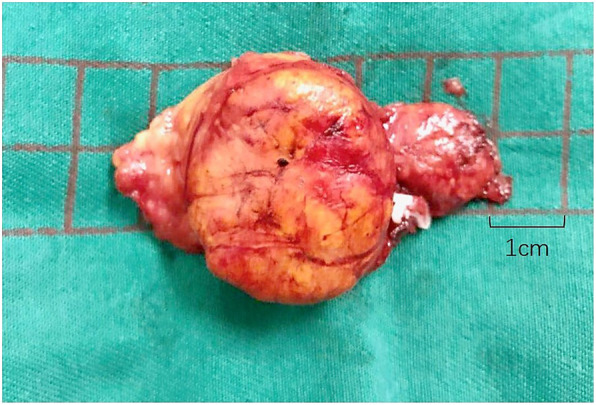

After discussing the medical and surgical management options, the patient decided to initially opt for medical management. She took spironolactone and two other antihypertensive drugs. Five days later, the patient’s blood pressure fell to 142/85 mmHg, and potassium had risen to 3.93 mmol/L. Despite initial good control of hypertension, blood pressures rose again and after 8 m of medical treatment, the patient elected to undergo left laparoscopic adrenalectomy. The tumor, which was about 3 cm in diameter, was in the middle of the adrenal gland (Fig. 3). Adrenocortical adenoma was confirmed histopathologically.

Fig. 3.

Left adrenal gland after laparoscopic adrenalectomy in 2017. The solid nodule had a diameter of 3 cm and was confirmed histopathologically to be an adrenocortical adenoma